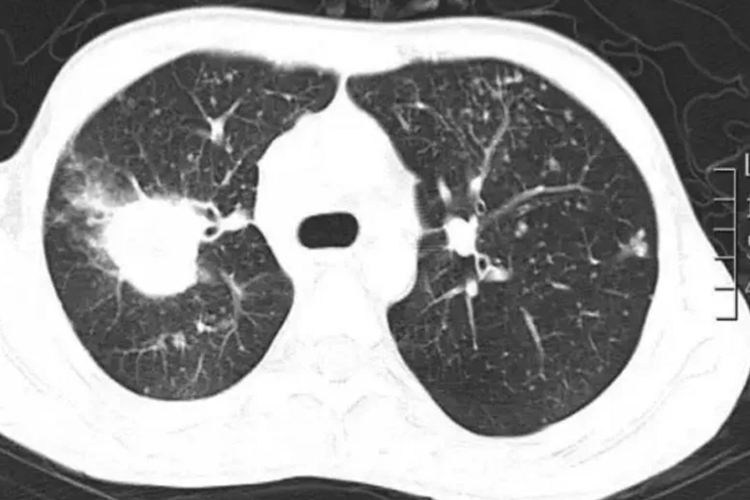

CT表现为双侧肺间质和实质浸润,可为支气管肺炎的小斑片影,单侧或双侧节段性实变,边缘模糊,密度不均以中下肺为多见,病灶可融合,一般不侵犯肺尖。肺实变阴影可以在短期内改变形状,一处消散而在另一处出现新病灶,但形成空洞者较少见。